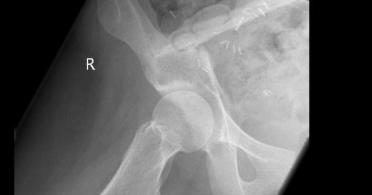

vermelden. Ich erinnert euch alle an die Bilder, die wir euch nach der Operation gezeigt haben. Hier ist es auf dem Foto noch einmal zu

sehen. Es ist ihr operativ das rechte Wadenbein aus dem Bein entfernt und als Stütze in das Becken eingesetzt worden, dort, wo vorher

die Beckenschaufel war. Das ist schon ein Meisterwerk ärztlicher Kunst gewesen. Und Gott hat Gelingen und Segen dazu gegeben. Die

Schmerzen, die Puschel in den letzten Tagen mehr hatte als sonst, rühren jetzt daher, dass der Knochen etwa an der Stelle, auf die der

Pfeil zeigt, richtiggehend durchgebrochen ist. Die Ärzte sprechen von einem Ermüdungsbruch. Der Knochen ist in der Substanz während

der Zeit der Chemo und der dadurch beabsichtigten Verhinderung der Neubildung von Zellen (Zielpunkt waren natürlich die

Krebszellen) zurückgegangen und ermüdet. Das große Problem ist, dass nun noch weniger Stabilität da ist und der Knochen erst wieder